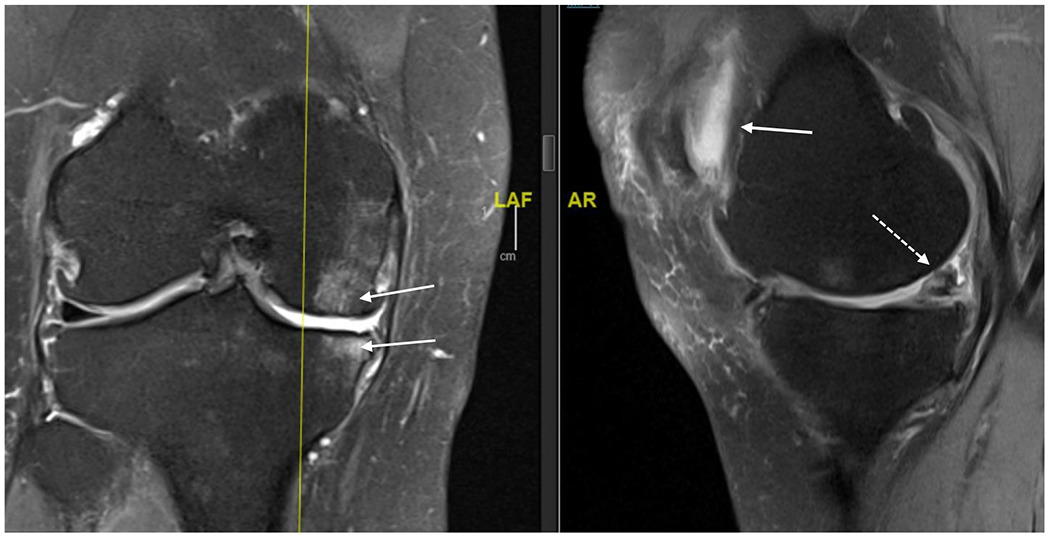

OA arises from complex biological processes that include cartilage, bone, synovium, ligaments, periarticular fat, meniscus, and muscle.15 The classic features of OA noted on radiographs include joint space narrowing due to loss of articular cartilage and meniscus, and bony changes including sclerosis of subchondral bone and osteophytes (Figure 1A). The effects of OA on cartilage, meniscus, syovium, subchondral bone and other structures can be appreciated on magnetic resonance imaging (Figure 1B).

연골, 반월상 연골, 활막, 연골하 뼈 및 기타 구조에 대한 OA의 영향은

자기공명영상에서 확인할 수 있습니다(그림 1B).

Figure 1B:

MRI (proton density, fat saturated) of right knee of 63 year old female. Coronal view on left and saggital view on right. Bone marrow lesions are identified with thin, solid white arrows on the coronal view; meniscal damage and cartilage damage are identified with dashed arrow on saggital view and retropatellar effusion as solid arrow on saggital view.

The biomechanical environment influences the disease process. Varus alignment of the lower extremities (“bowlegged”) shifts load medially, increasing risk of medial compartment knee OA, while valgus alignment (“knocked knees”) shifts load laterally leading to lateral compartment OA. These abnormalities in alignment are risk factors for OA incidence and, more importantly, for OA progression.16,17 Excessive loading of bone may result in bone marrow lesions, seen on magnetic resonance imaging (Figure 1B).18 Histologically, bone marrow lesions contain microfractures with bone fragments, necrosis, fibrosis and abnormal adipocytes suggestive of focal areas of damage and remodeling due to abnormal loading.19

63세 여성의 오른쪽 무릎 MRI(양성자 밀도, 지방 포화도). 왼쪽은 관상면, 오른쪽은 시상면입니다. 골수 병변은 관상면에서 가늘고 단단한 흰색 화살표로, 반월상 연골 손상과 연골 손상은 시상면에서 점선 화살표로, 후방 슬개골 삼출은 시상면에서 실선 화살표로 식별할 수 있습니다.

과도한 뼈의 하중은 자기 공명 영상에서 볼 수 있는 골수 병변을 초래할 수 있습니다(그림 1B).18 조직학적으로 골수 병변에는 골절, 괴사, 섬유증 및 비정상적인 지방 세포가 있는 미세 골절이 포함되어 비정상적인 하중으로 인한 국소 손상 및 리모델링을 시사합니다.19

MRI is seldom indicated in the assessment or management of knee or hip OA. MRI detects changes in cartilage, meniscus (knee), labrum (hip), bone and synovium, providing a fuller picture of pathological involvement (Figure 1B).36 Because of its high sensitivity36, MRI is useful for research studies to identify early OA and document structural changes over time. In clinical care, MRI can be useful if there is suspicion of conditions such as subchondral insufficiency fracture, tumor or infection that would be treated differently and more urgently than OA.